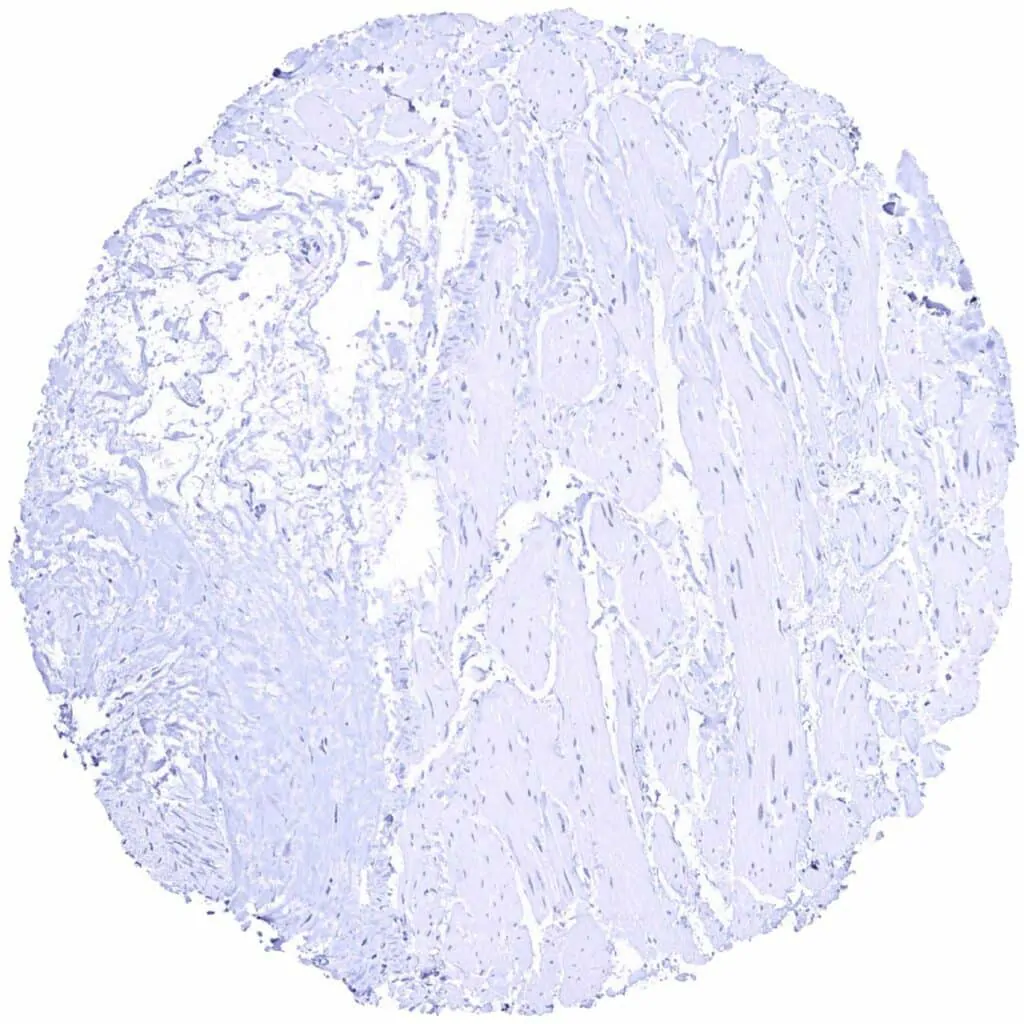

Urinary bladder, muscular wall